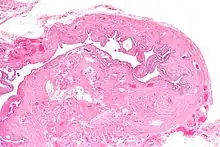

| Micrograph of salpingitis isthmica nodosa, showing the characteristic nodular thickening. H&E stain. | |

Salpingitis isthmica nodosa (SIN), also known as diverticulosis of the fallopian tube, is nodular thickening of the narrow part of the uterine tube, due to inflammation.

It is characterized by nodular thickening of the tunica muscularis of the narrow (isthmic) portion of the fallopian tube. In severe cases, it leads to complete obliteration of the tubal lumen. It is uncommonly bilateral.[2]